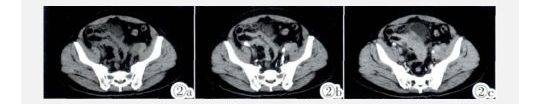

图2a~2c 回肠壁不均匀增厚,厚约1.35 cm,平扫CT值约38HU,增强扫描可见轻度强化,CT值约为60HU,周围脂肪间隙模糊、密度增高,受累回肠与膀胱病变分界不清。